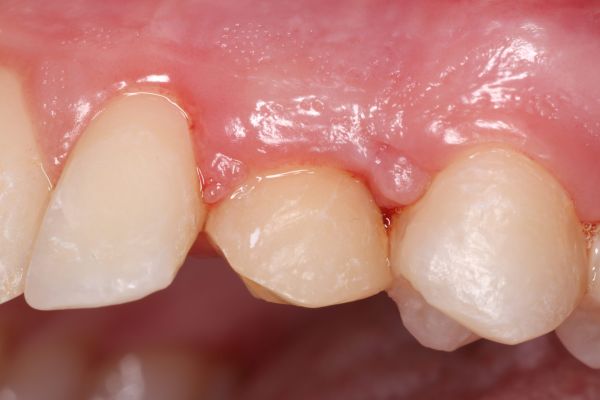

As best clinical case, Garrido Martínez, et al. are the first winners with an excellent clinical case on the maxillary reconstruction of a patient with subperiosteal implants. Anitua repeats the award with a clinical case where they successfully show the explantation of a poorly positioned implant in the aesthetic sector and its subsequent regeneration.